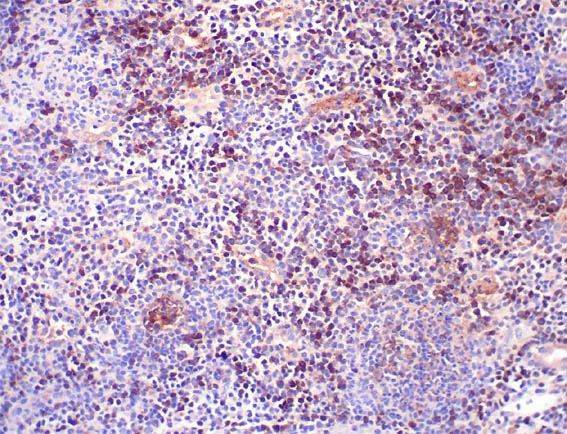

Figure 14. Immunohistochemistry for CD138, X200.